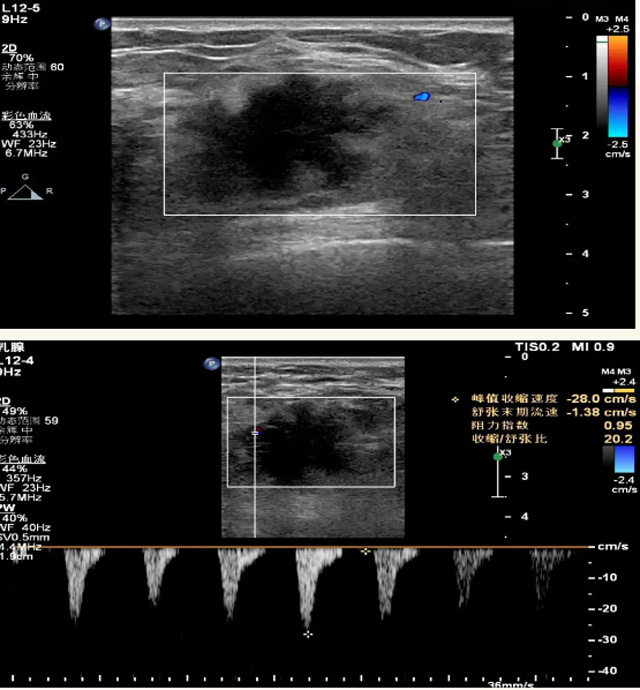

乳腺B超檢查無輻射,對囊性病變敏感,可以實(shí)時(shí)觀察病灶。超聲引導(dǎo)活檢跟手術(shù)前的定位。就是它對于微小的鈣化查出率比鉬靶稍微差點(diǎn)。磁共振MRI檢查也是是沒有輻射的,對備孕跟已經(jīng)懷孕的人士比較友好。不用擔(dān)心這個(gè)輻射影響胎兒問題。對乳腺病灶敏感性較高,致密乳腺病灶、乳腺癌的復(fù)發(fā),準(zhǔn)確鑒別囊性及實(shí)性病變??梢詭椭R床醫(yī)生判斷惡性、良性病變。但是MRI磁共振對微小鈣化不明顯,微鈣化還是鉬靶靠譜點(diǎn)。檢查時(shí)間比較長,有偽影的影響。費(fèi)用相對B超,鉬靶高很多。

乳腺B超

磁共振MRI